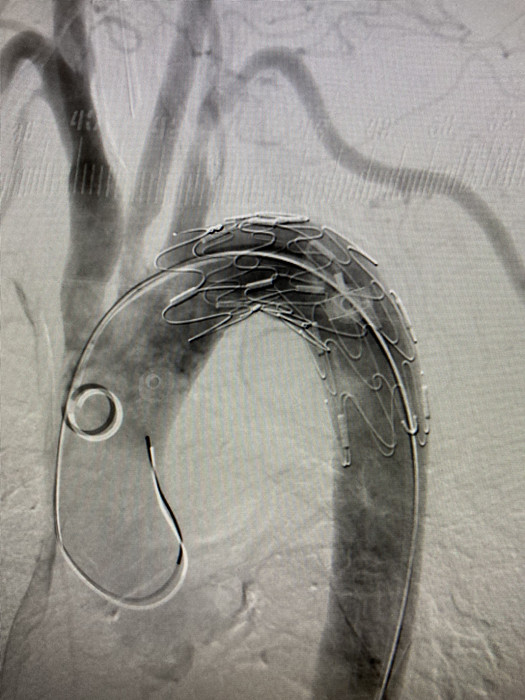

“如果內(nèi)鏡下直接取出異物容易造成患者二次損傷,刺向胸主動(dòng)脈的鴨骨頭最為尖銳,距離主動(dòng)脈壁最近,一旦刺破可引發(fā)致命性大出血?!苯?jīng)消化內(nèi)科、血管外科、心胸外科、放射科、麻醉科等科室緊急會(huì)診,決定為劉奶奶先行胸主動(dòng)脈支架術(shù),后在內(nèi)鏡下行食管異物取出術(shù)。

凌晨4點(diǎn),血管外科副主任醫(yī)師程國兵,主治醫(yī)師李曉陽,為劉奶奶進(jìn)行了胸主動(dòng)脈支架植入手術(shù),歷經(jīng)1小時(shí),手術(shù)順利結(jié)束。